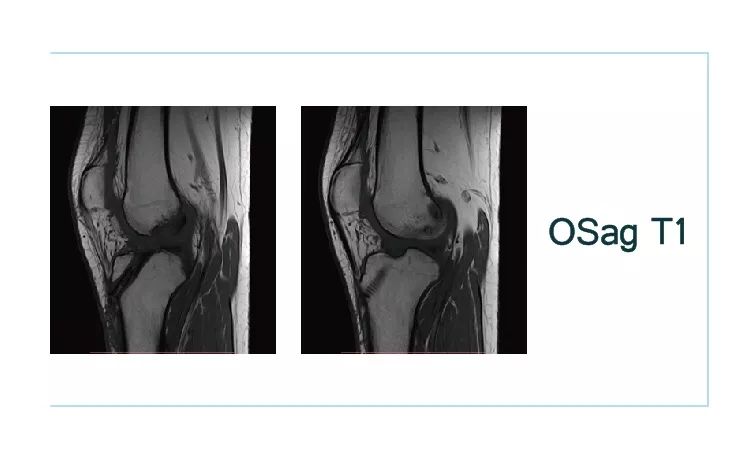

【朗润影像档案】20180914磁共振影像病例讨论结果